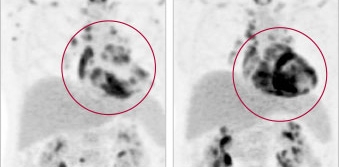

PET scan of cardiac sarcoidosis

1. Making the Diagnosis: Why Cardiac Sarcoidosis Should Be on Cardiologists’ Radar

Building knowledge and awareness of an under-recognized heart condition